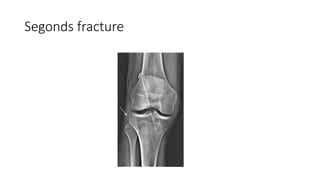

• 1)X-ray of the knee-Anteroposterior and lateral view

• See for seconds fracture-Avulsion fracture if lateral capsular ligament

of knee which is ACL insertion site

Segonds fracture

Investigations • 1)X-ray ofthe knee-Anteroposterior and lateral view • See for seconds fracture-Avulsion fracture if lateral capsular ligament of knee which is ACL insertion site • • Deep Lateral sulcus sign-Depression of lateral femoral condyle.